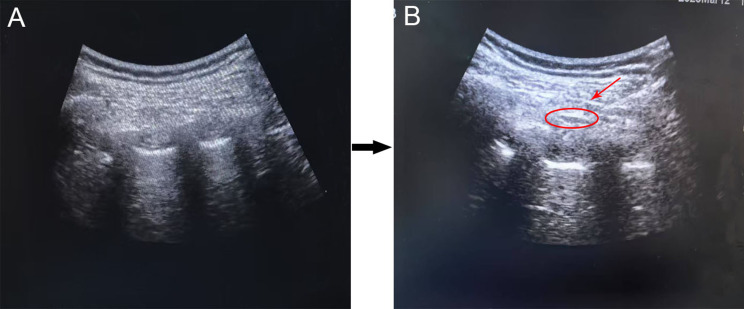

Methods: A total of 89 patients with the American Society of Anesthesiologists (ASA) physical status I-III were randomly assigned to two groups. The DR group received an intercostal nerve block with a mixture of 20 mL of 0.25% ropivacaine and 2 μg/kg of DEX, while the RP group received 20 mL of 0.25% ropivacaine alone. Plasma levels of epinephrine (E), norepinephrine (NE), and cortisol (COR) were measured perioperatively. Postoperative analgesia was assessed using the Visual Analog Scale (VAS), the cumulative dose of rescue analgesics, and the pump pressure required for rescue analgesia. Additionally, adverse events and satisfaction scores from both patients and thoracic surgeons were recorded. The Shapiro-Wilk test was applied for uniformly distributed. The values for baseline information were presented as the mean ±standard (SD), and compared using one-way ANOVA. Enumeration data were expressed as percentages or frequencies and compared using the Chi-square test.